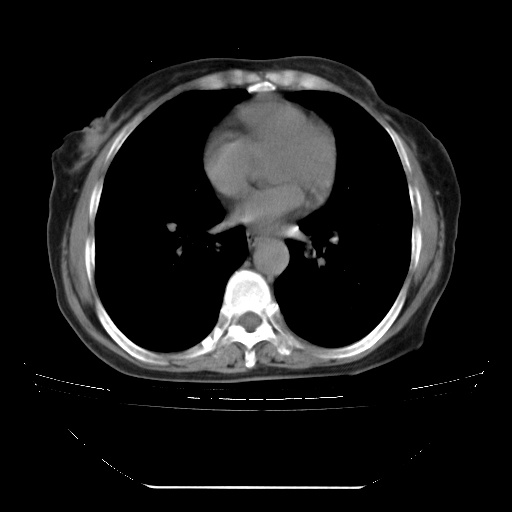

患者女性,72岁,慢性咳嗽3月余,曾抗炎治疗无效果,最近抗结核治疗约半月余,症状缓解。

ct示两肺粟粒状病灶,以两肺上叶尖后段及下叶背段分布为主;首先考虑结核。请战友们分析。

两肺内病灶呈小结节状和树芽状,纵膈的肿大的淋巴结密度不均匀,并见有钙化,考虑为两肺结核可能更大些。

两肺内病灶呈小结节状和树芽状,纵膈的肿大的淋巴结密度不均匀,并见有钙化,多形态病灶,考虑为两肺结核,肝内考虑小囊肿。

片子很好,质量很高,两侧肺门淋巴结肿大并有钙化,两肺弥漫病灶,首先考虑tb并播散,但年龄大了呀(72岁)小细胞肺癌不能除外,如果是肺癌也没什么大的治疗了,建议正规抗结核治疗后复查

两肺内病灶呈小结节状和树芽状,纵膈的肿大的淋巴结密度不均匀,并见有钙化,结合(曾抗炎治疗无效果,最近抗结核治疗约半月余,症状缓解。)

考虑为两肺结核可能更大些。

纵隔见肿大淋巴结并钙化,首先考虑结核,但感觉小结节像“挂果”征,分布位于支气管边缘,所以不排外肺泡癌,建议抗唠后复查吧?不然是癌的话,也不好治吧?化疗?